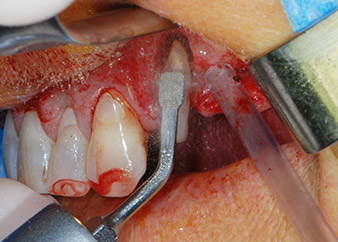

Въпреки това, ние се придържахме към първоначалния си план да запазим и двата зъба като абатмънти за временен мост по време на 6-месечната остеоинтеграция на имплантите. При повторна интервенция, ситуацията трябва да се преразгледа. Първо, в опит да се овладее ендо-перио проблема, останалата повърхност на зъба е внимателно обработена с пиезохирургично оборудване (Piezomed, W&H, използван с накрайник S1 под формата на шпатула, първоначално проектиран за ерозия на латералната синусна стена) (Фиг. 4).

След това апексът се изпилява със същия инструмент, за да се отстрани остатъчната инфектирана апикална тъкан и да се намали възможното допълнително усложнение по кореновите канали (апикоектомия) (Фиг. 5). Ретроградно запълване не е необходимо, защото ортоградното запълване току-що е ревизиран.